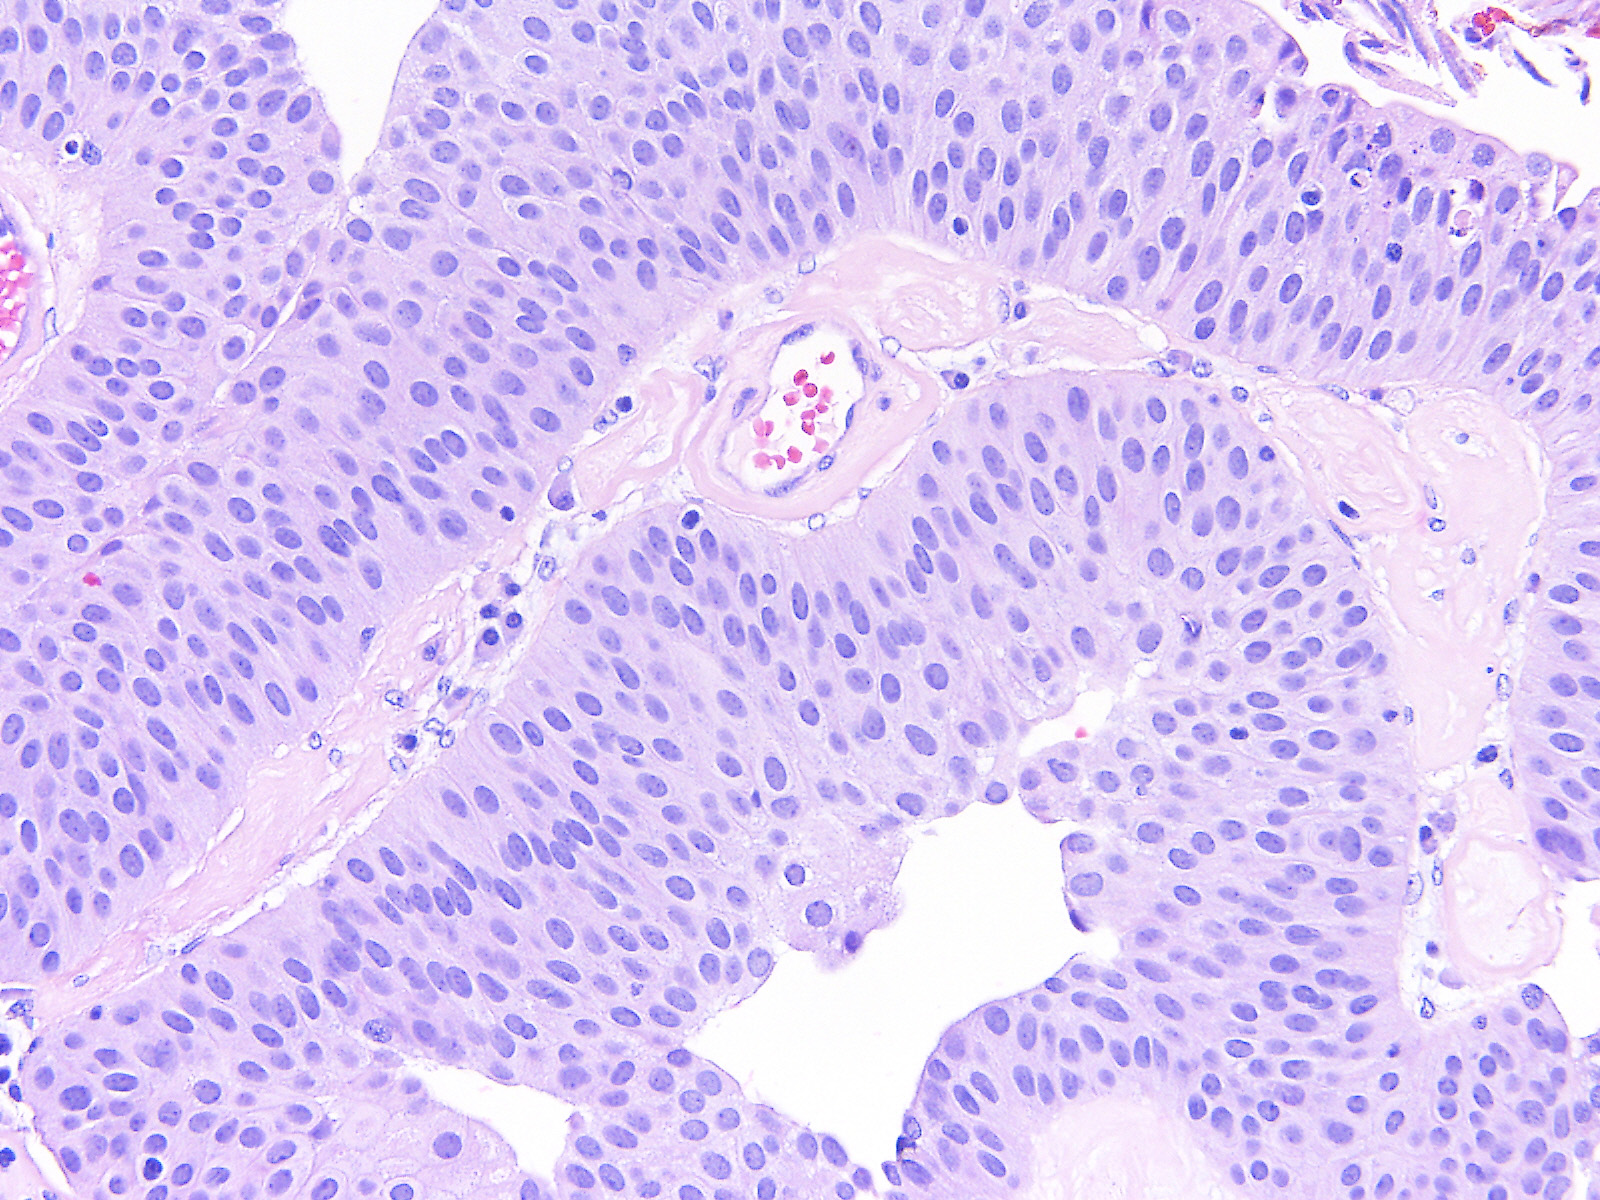

Consensus grade: Low-grade papillary urothelial carcinoma (LG-PUC)

A 74 year-old woman underwent a TURBT.